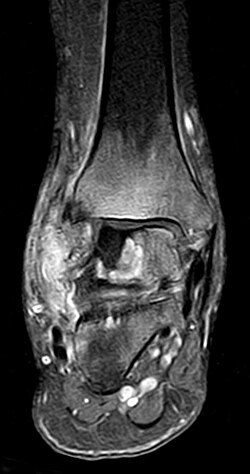

| Aseptische Knochennekrose - sagittale MRT (T1 Spinecho-Sequenz) einer aseptischen Knochennekrose mit Befall der distalen Tibia bei einem 13-jährigen Kind mit akuter lymphatischer Leukämie (ALL) . | Eigenes Werk | Christaras A | Datei:AON distal tibia - MR T1 SE sagittal - 13yr child with ALL.jpg | |